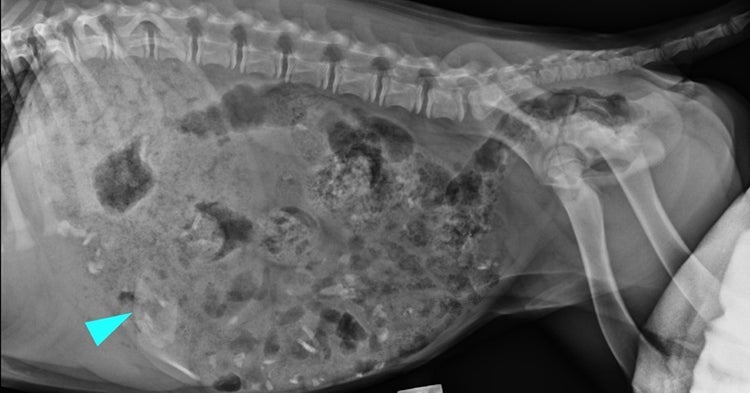

When he arrived at BVS, Marlo underwent a series of investigations. An ultrasound revealed his stomach was markedly distended and filled with a large amount of kibble. A lateral abdominal radiograph confirmed the foreign body – later measured at a sizeable 6.5cm by 3.5cm – was still inside the stomach.